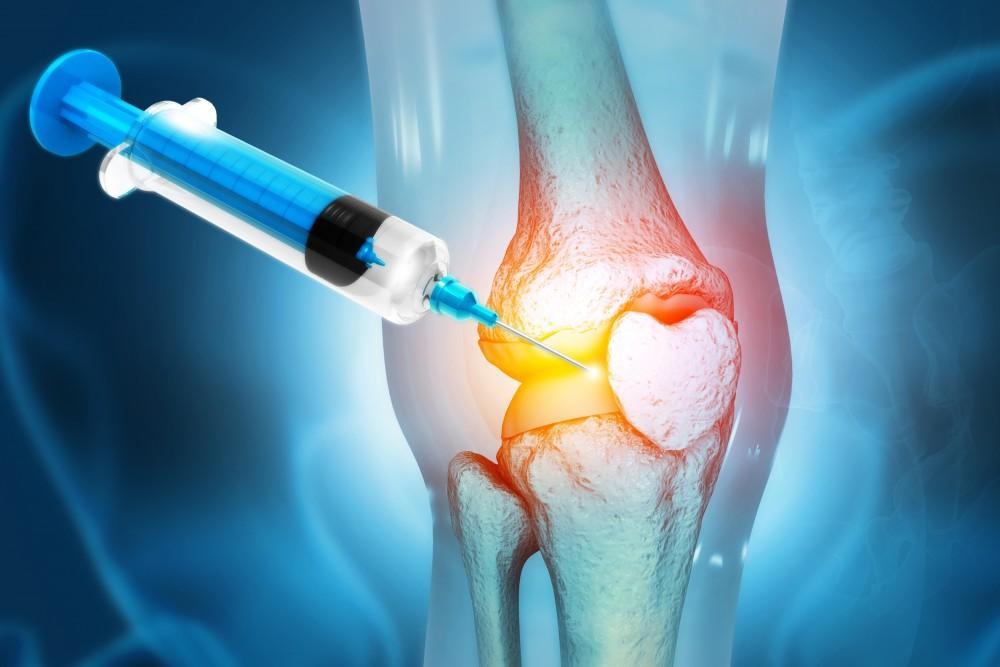

درمان آرتروز زانو با پی آر پی

پی ارپی (Platelet-Rich Plasma یا PRP) یکی از روشهای درمانی نوین برای درمان ارتروز زانو است. این درمان به شرح زیر انجام میشود:

تزریق پلاسمای غنی از پلاکت:

– پلاسمای غنی از پلاکت به محل ضایعه ارتروز در زانو تزریق میشود.